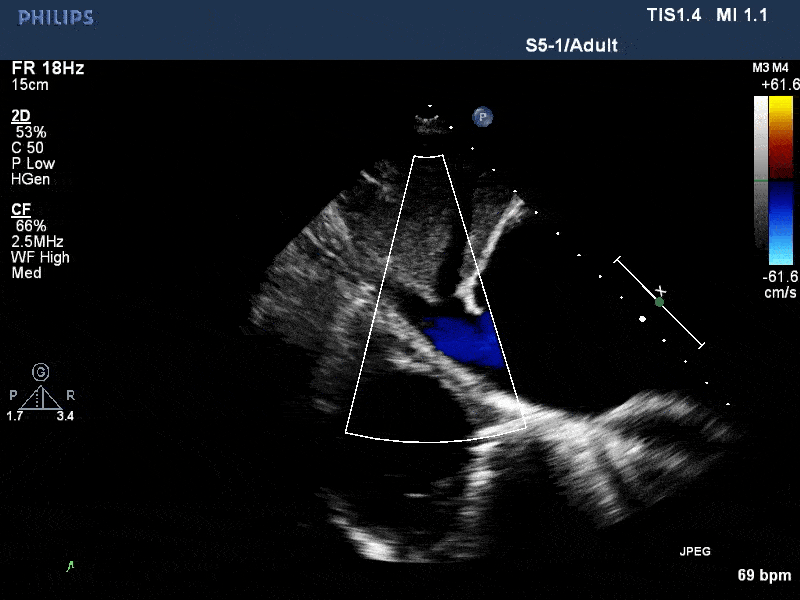

术前与术后30天门静脉反流比较

术前超声:肝门静脉重度反流